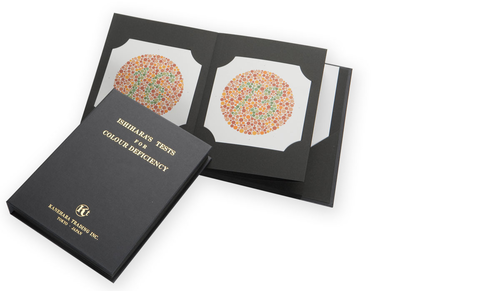

Ishihara Book

Ishihara Book